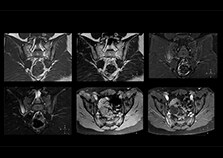

“On average, we scan about 80 patients per day, but on some days we scan well over 100 patients. The scanner is in use 7 days per week, operated 20 hours per day on week days and 8 hours per day in the weekend,” Mr. Tuna says.   “To avoid coil changes we plan examinations of similar anatomies back to back, such as head and spine. Multiva helps us here a lot because coils don’t need to be changed frequently. Moreover, thanks to parallel imaging technology and 16-channel HeadSpineTorso and 8-channel MSK coils we are able to achieve excellent image quality. In this way Multiva helped us to increase both image quality and productivity.”   “Neurological cases, such as brain and spine imaging, represent the largest share in our MR scanning, followed by musculoskeletal cases. In general, we use simple and basic imaging protocols. But occasionally, we use advanced techniques for problematic cases if necessary.

“Since we have Multiva, we have improved our workflow, because it has been so easy for our operators to learn and use Multiva. Our operators notice that the coils are lightweight and coils don’t need to be changed frequently. The user interface is easy to use. Features like this help us to scan a high number of patients. For instance, the musculoskeletal coils can be used interchangeably, and due to the user-friendly interface, the number of mistakes such as, for example, correct coil element selection has decreased significantly, because the system does it automatically by itself.”    “Most important, Multiva satisfies our clinical imaging needs very well,” says Mr. Tuna. “Many features of Multiva have become similar to the Ingenia system. Even in more complex imaging such as abdominal and cardiac, the image quality and performance of Multiva is better than we expected. General surgeons and physicians from our hospital’s internal medicine department prefer to refer to us because of this.”

“Overall, Multiva provides what we need in term of patient needs and even potential needs,” says Mr. Tuna. “It allows us to scan a high patient volume and image a large variety of anatomies and conditions.”   “Our goal is to achieve uncompromising quality based on universal standards, while solving clinically complex cases. Our Multiva scanner allows high productivity with fast imaging time, and allows us to make confident diagnoses in a broad range of cases.”   “It’s an excellent multi-purpose scanner that satisfies all our MR imaging requirements in the hospital,” he concludes.